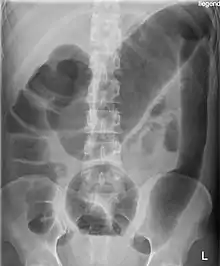

There may be signs of septic shock. A physical examination reveals abdominal tenderness and possible loss of bowel sounds. An abdominal radiography shows colonic dilation. White blood cell count is usually elevated. Severe sepsis may present with hypothermia or leukopenia.

Massively dilated colon with air-fluid level can be seen on abdominal radiograph or CT scan.[5][6]